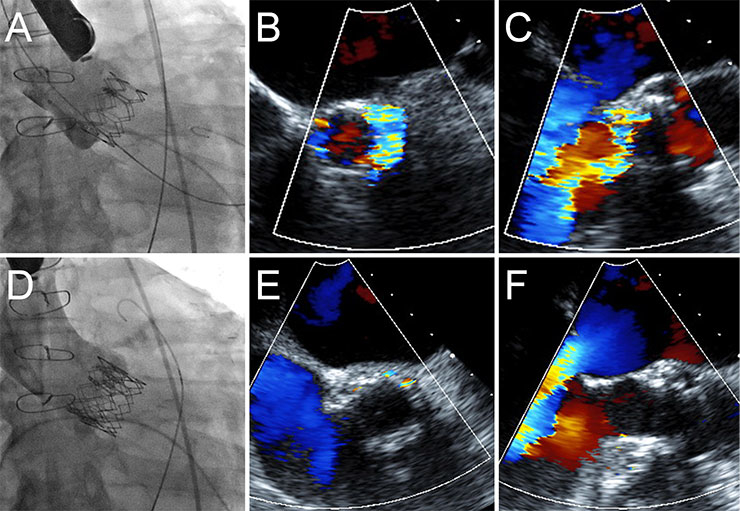

Figure 2

Treatment of paravalvular regurgitation by implantation of a second transcatheter heart valve. In patient, the TEE measured an annulus of 22 mm. A 26 mm Edwards Sapien XT valve was implanted (A). A low implantation resulted in severe paravalvular aortic regurgitation (B, C). A second 26 mm valve was subsequently implanted in a higher position, thus extending the annular seal (D) resulting in a mild paravalvular leak (E, F).